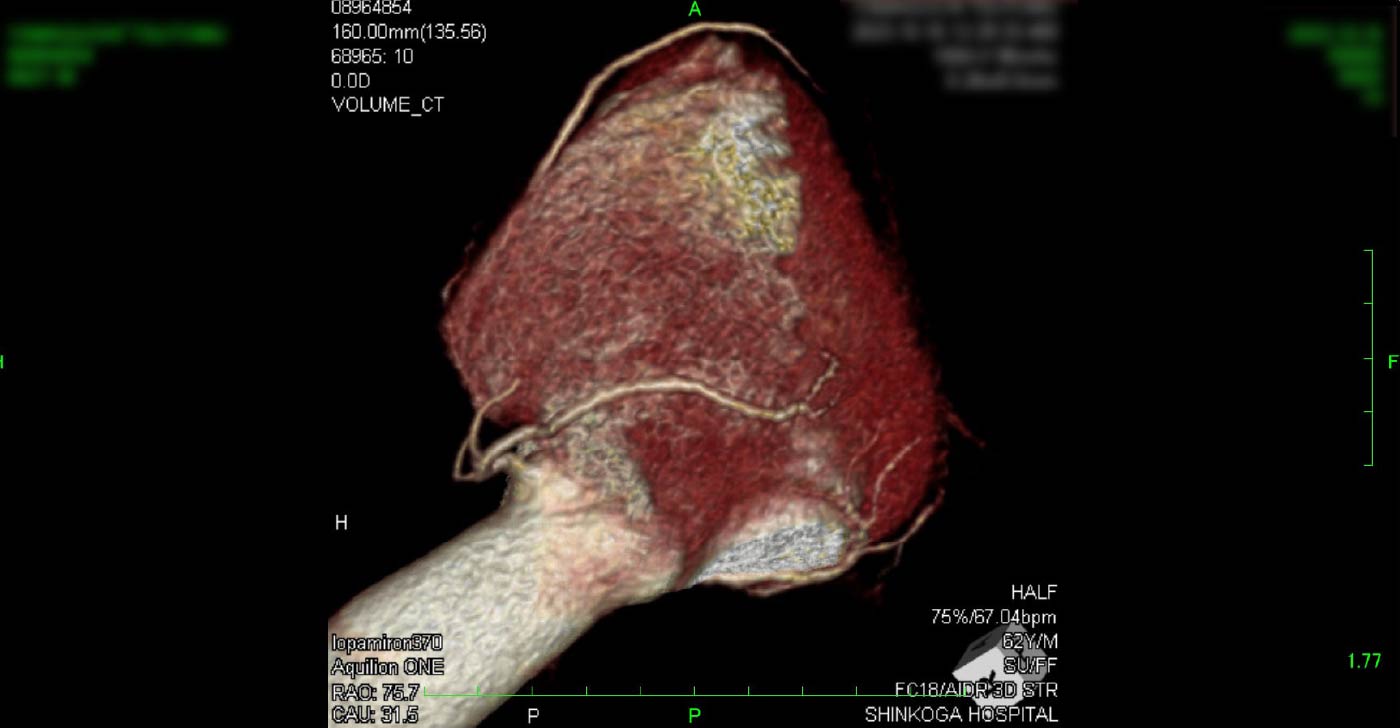

進行期 造影心臓CT 重症心筋虚血症例

冠動脈CT

狭心症を安全に診断あるいは除外する!

連携施設の新古賀病院で速やかに実行可能です。